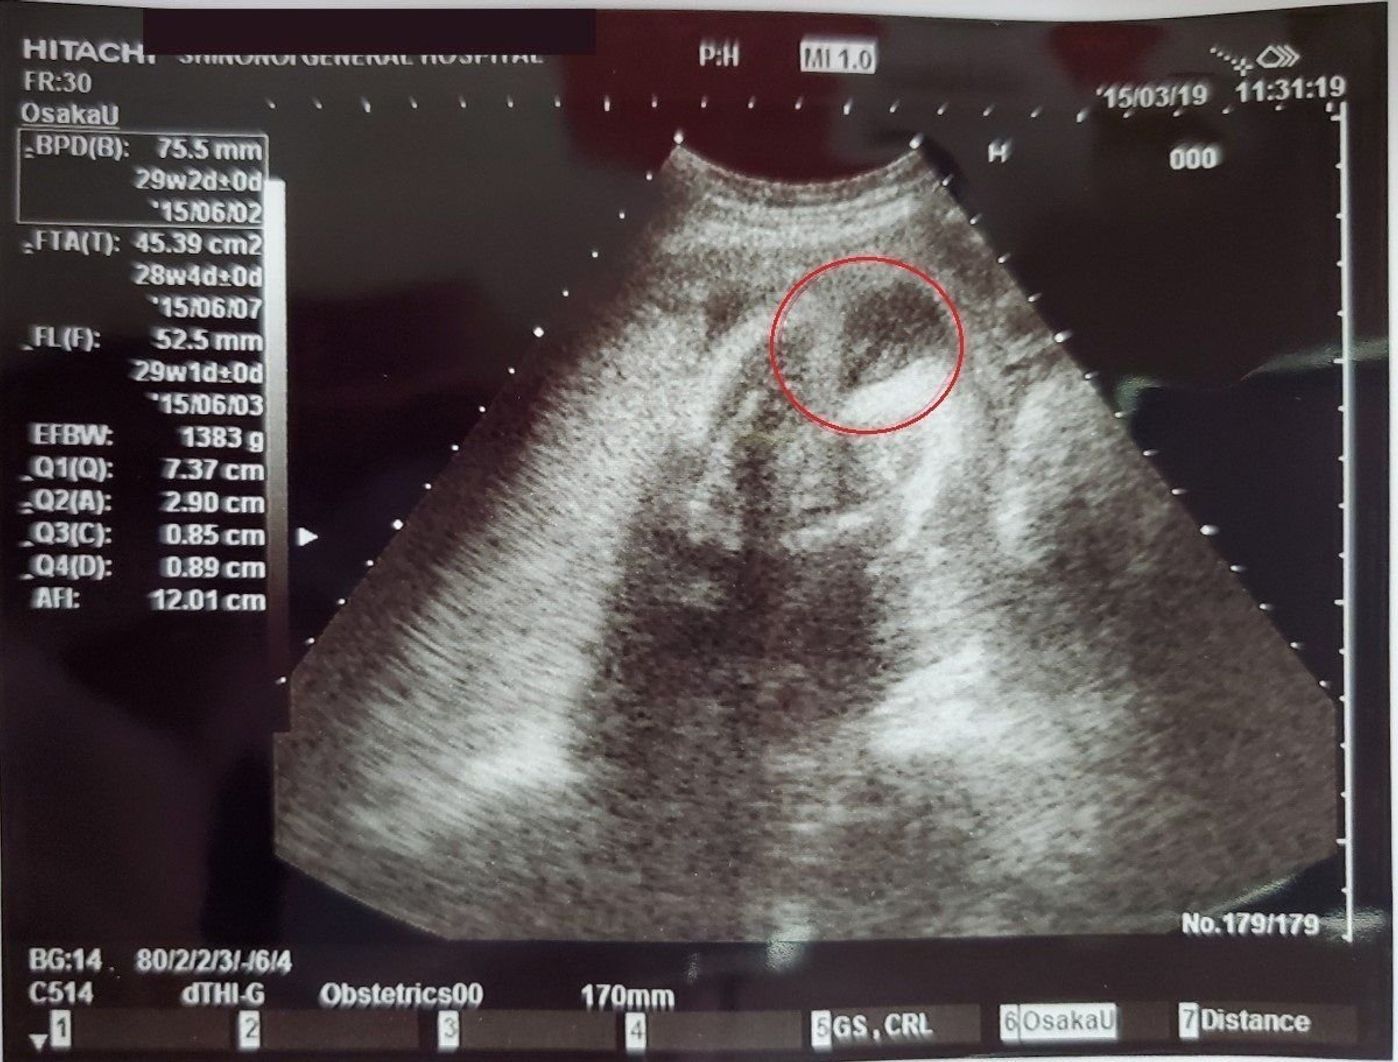

妊娠27週目(27w0d~6d)のエコー写真とエピソード|妊娠7ヶ月 妊娠27週目は、妊娠7ヶ月の最終週です。 胎児は、羊水の中でいろんな動きができるようになっています。 痛いほどの強い胎動を感じている妊婦さんもいらっしゃるでしょう。 赤ちゃんが活発に動き回っている証拠です! また、この頃になるとお腹の張りを感じることが増えてきます。 体重管理のため妊娠27週の胎児の体重について 経験者の方がいらっしゃいましたら教えてください。 今27週ちょうどになります。本日検診に行ったところ胎児の体重が1300gを超えていました。先生に聞いたところ平均よりもだいぶ重いとの 今日で39週6日になりました! 昨日の検診で胎児の重さが2462g 初期の 妊娠27週目の胎児の大きさや体重、成長の様子についてご紹介します。 胎児の大きさ (FL:大腿骨長):約42〜53mm 体重:約740〜1,300g

妊娠週数別の胎児体重の基準値(超音波検査法による) 3 つの線は sd、平均値、 sd を順に表しています。(sd:標準偏差) 正常発育児の954% が± sd の範囲にはいります。 (正常児の約98%が一番下の線よりも上にはいるということを表しています) 妊娠週数 sd 平均値 sd 18週E妊娠top エコー写真 妊娠27週4日 妊娠27週4日(27w4d)の超音波(エコー)写真 写真27w4dぽんさん1450g あなたのエコー写真も投稿してみませんか! 妊娠週&出産カウントダウンの設定 妊娠27w4d おなまえポン;妊娠38週 平均体重:28g(基準値:2181g~3494g) 妊娠39週 平均体重:29g(基準値:2292g~3685g) 妊娠40週 平均体重:3125g(基準値:23g~3862g) 妊娠41週 平均体重:3244g(基準値:2465g~4023g) 出産時の胎児の平均体重について